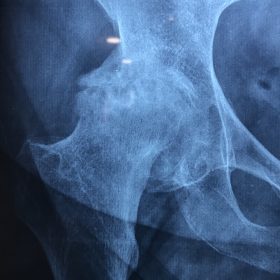

Διάγνωση- Σταδιοποίηση

Διακρίνονται σε 4 στάδια.

Στάδιο Ι. Στένωση του μεσαθριου διαστήματος

Στάδιο ΙΙ. Σκλήρυνση του υποκύμενου χόνδρου

Στάδιο ΙΙΙ. Σκλήρυνση του υπερκείμενου χόνδρου, καταστροφή του υποχόνδρινου οστούν, σχηματισμός οστεόφυτων, οίδημα αρθρώσεως και βραδυνός πόνος

Στάδιο IV. Οστική καθίζηση, καταστροφή μαλακών μορίων μυϊκών ομάδων, υπεξάρθρημα της αρθρώσεως και αλλαγή του μηχανικού άξονα